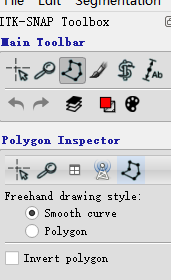

3. 1 多边形分割

- 选择的曲线为Smooth curve

- 使用多边形工具勾画以后,使用accept获取分割的区域

- 使用

paste last ploygon应用最后的轮廓

- 使用画笔工具进行涂画,选择不同的大小进行边界以及内容的填充,选择边界自适应填充可以根据不同的CT值,来填充不同的区域